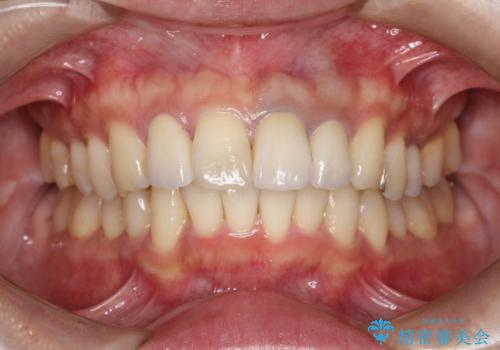

[MTMを行い歯の神経を保存] 歯周補綴ブリッジ